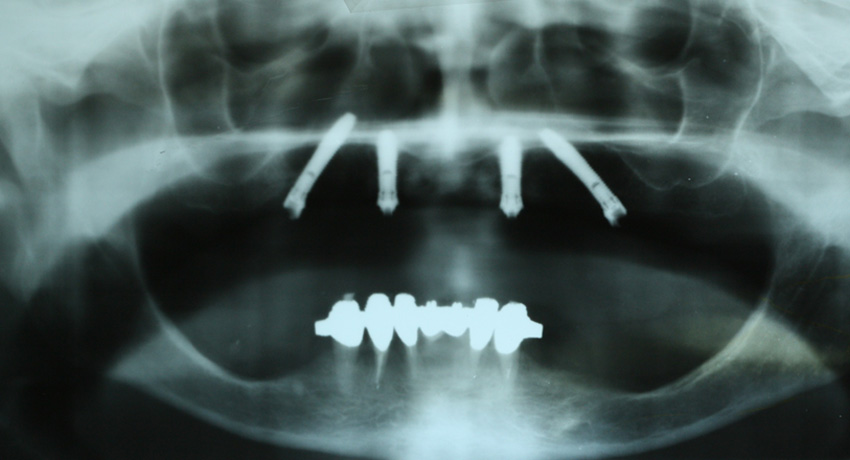

Terapia implanto-protesica “ALL ON FOUR” secondo Malò

Viene ricostruita un’arcata utilizzando solo 4 viti di cui due inserite in diagonale per evitare la fastidiosa operazione di rialzo del seno mascellare. Tale intervento ha richiesto la collaborazione dello specialista implanto-protesista.